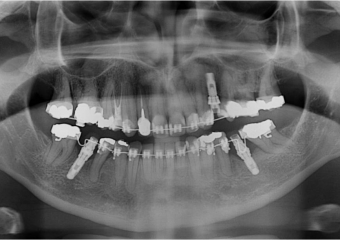

Raio x panorâmico inicial